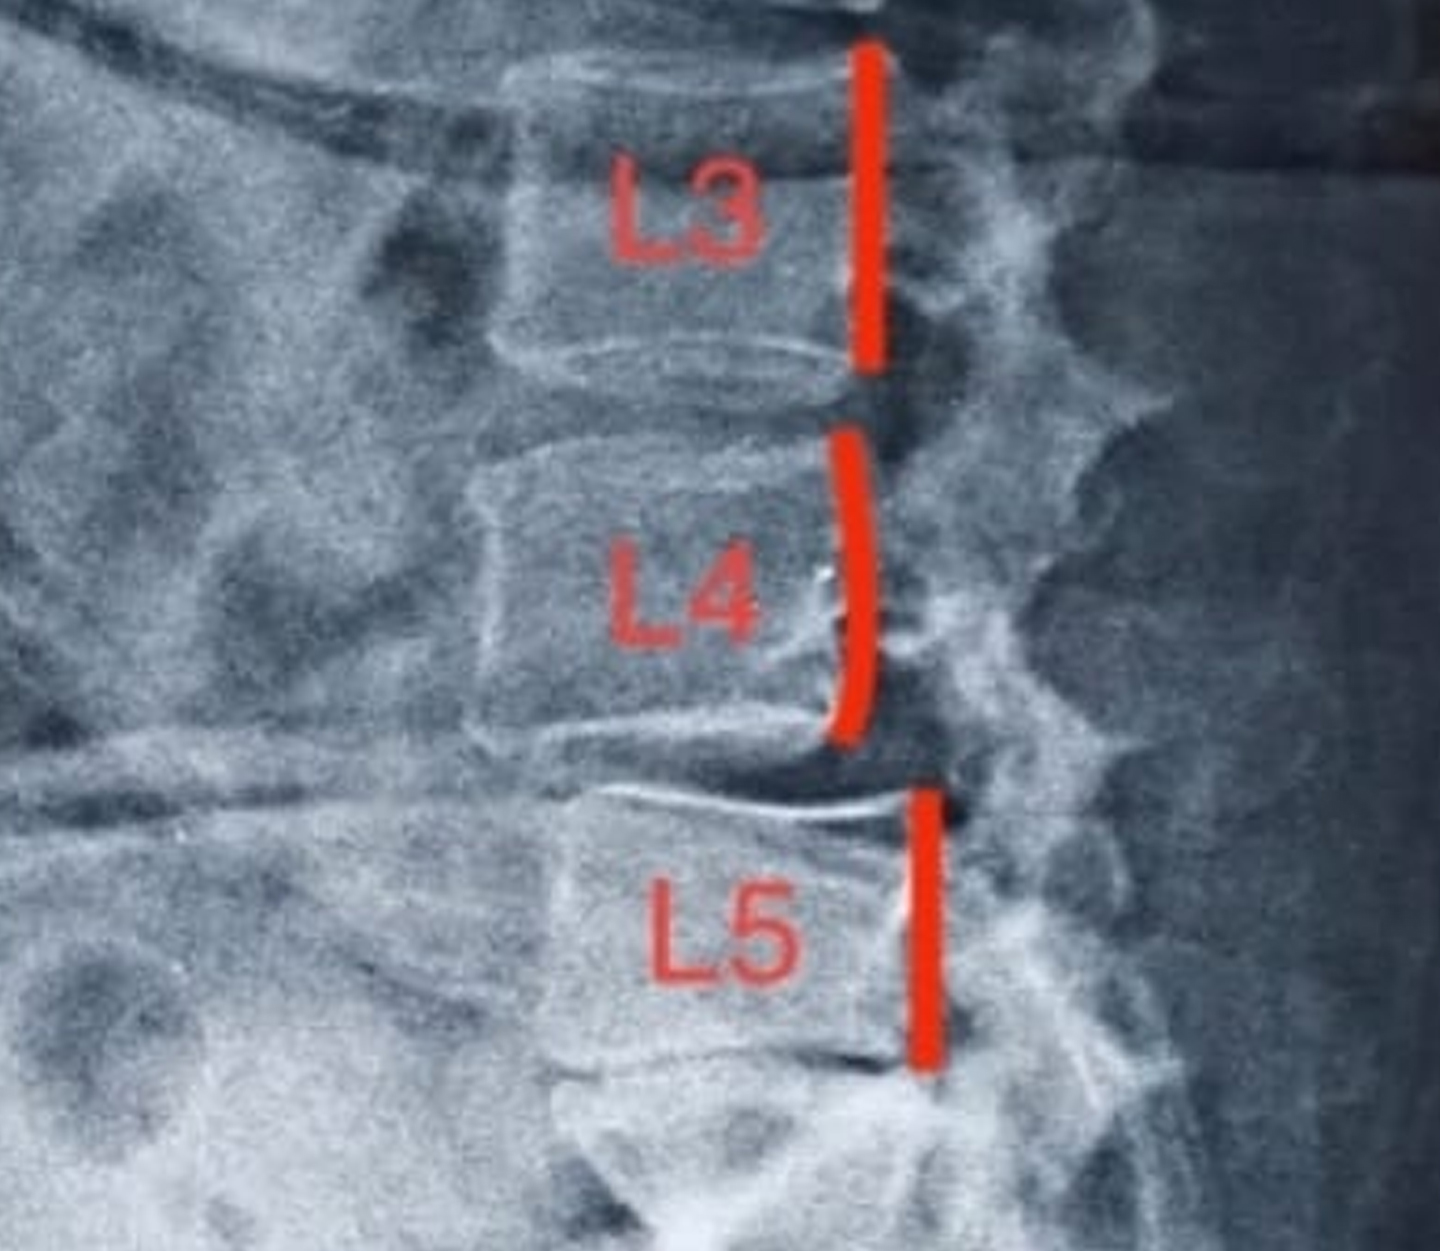

Case of Lytic L4–L5 Spondylolisthesis

At Verteva Spine & Ortho Care, we combine cutting-edge technology with expert surgical skill to deliver precise, minimally invasive solutions for spine disorders. This case highlights the journey of a 45-year-old woman suffering from debilitating lytic L4–L5 spondylolisthesis.

- Instability at the L4–L5 level due to a lytic pars defect